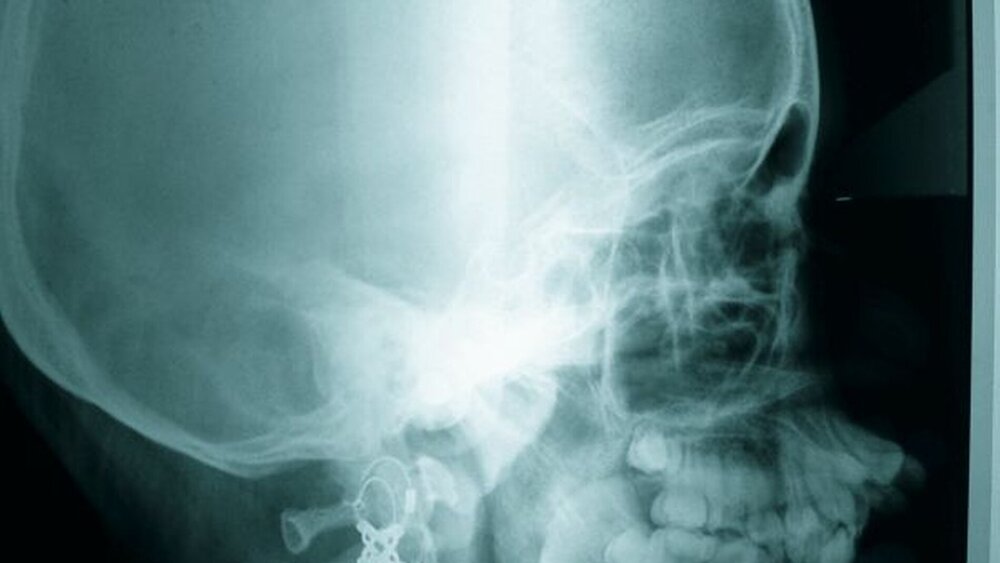

Die radiologische Untersuchung bestand aus einem Orthopantomogramm (OPTG), einer Aufbissaufnahme sowie einer Fernröntgenseitaufnahme (FRS). Neben der Übersicht der Gebissituation mit Nachweis des nicht durchgebrochenen Zahnes 22 im OPTG (Abbildung 3) war in der Aufbissaufnahme der Umfang der knöchernen Gaumenspalte klar zu erkennen (Abbildung 4). Das FRS ließ – bis auf die vertikal anterior verkürzte Maxilla und eine Protrusion der anterioren Prämaxilla – einen weitgehend normalen knöchernen Befund diagnostizieren (Abbildung 5).